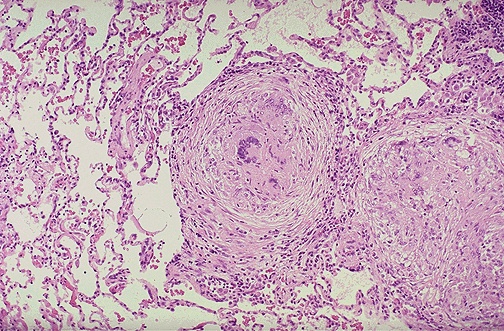

| Well-defined granulomas are seen here. They have rounded outlines. The one toward the center of the photograph contains several Langhans giant cells. Granulomas are composed of transformed macrophages called epithelioid cells along with lymphocytes, occasional PMN's, plasma cells, and fibroblasts. The localized, small appearance of these granulomas suggests that the immune response is fairly good. |